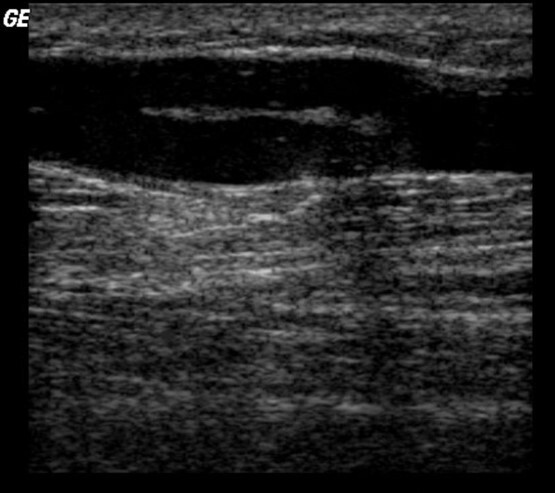

What is this a example of? (this is a GSV)

Residual Fibrous bands in recanalized GSV